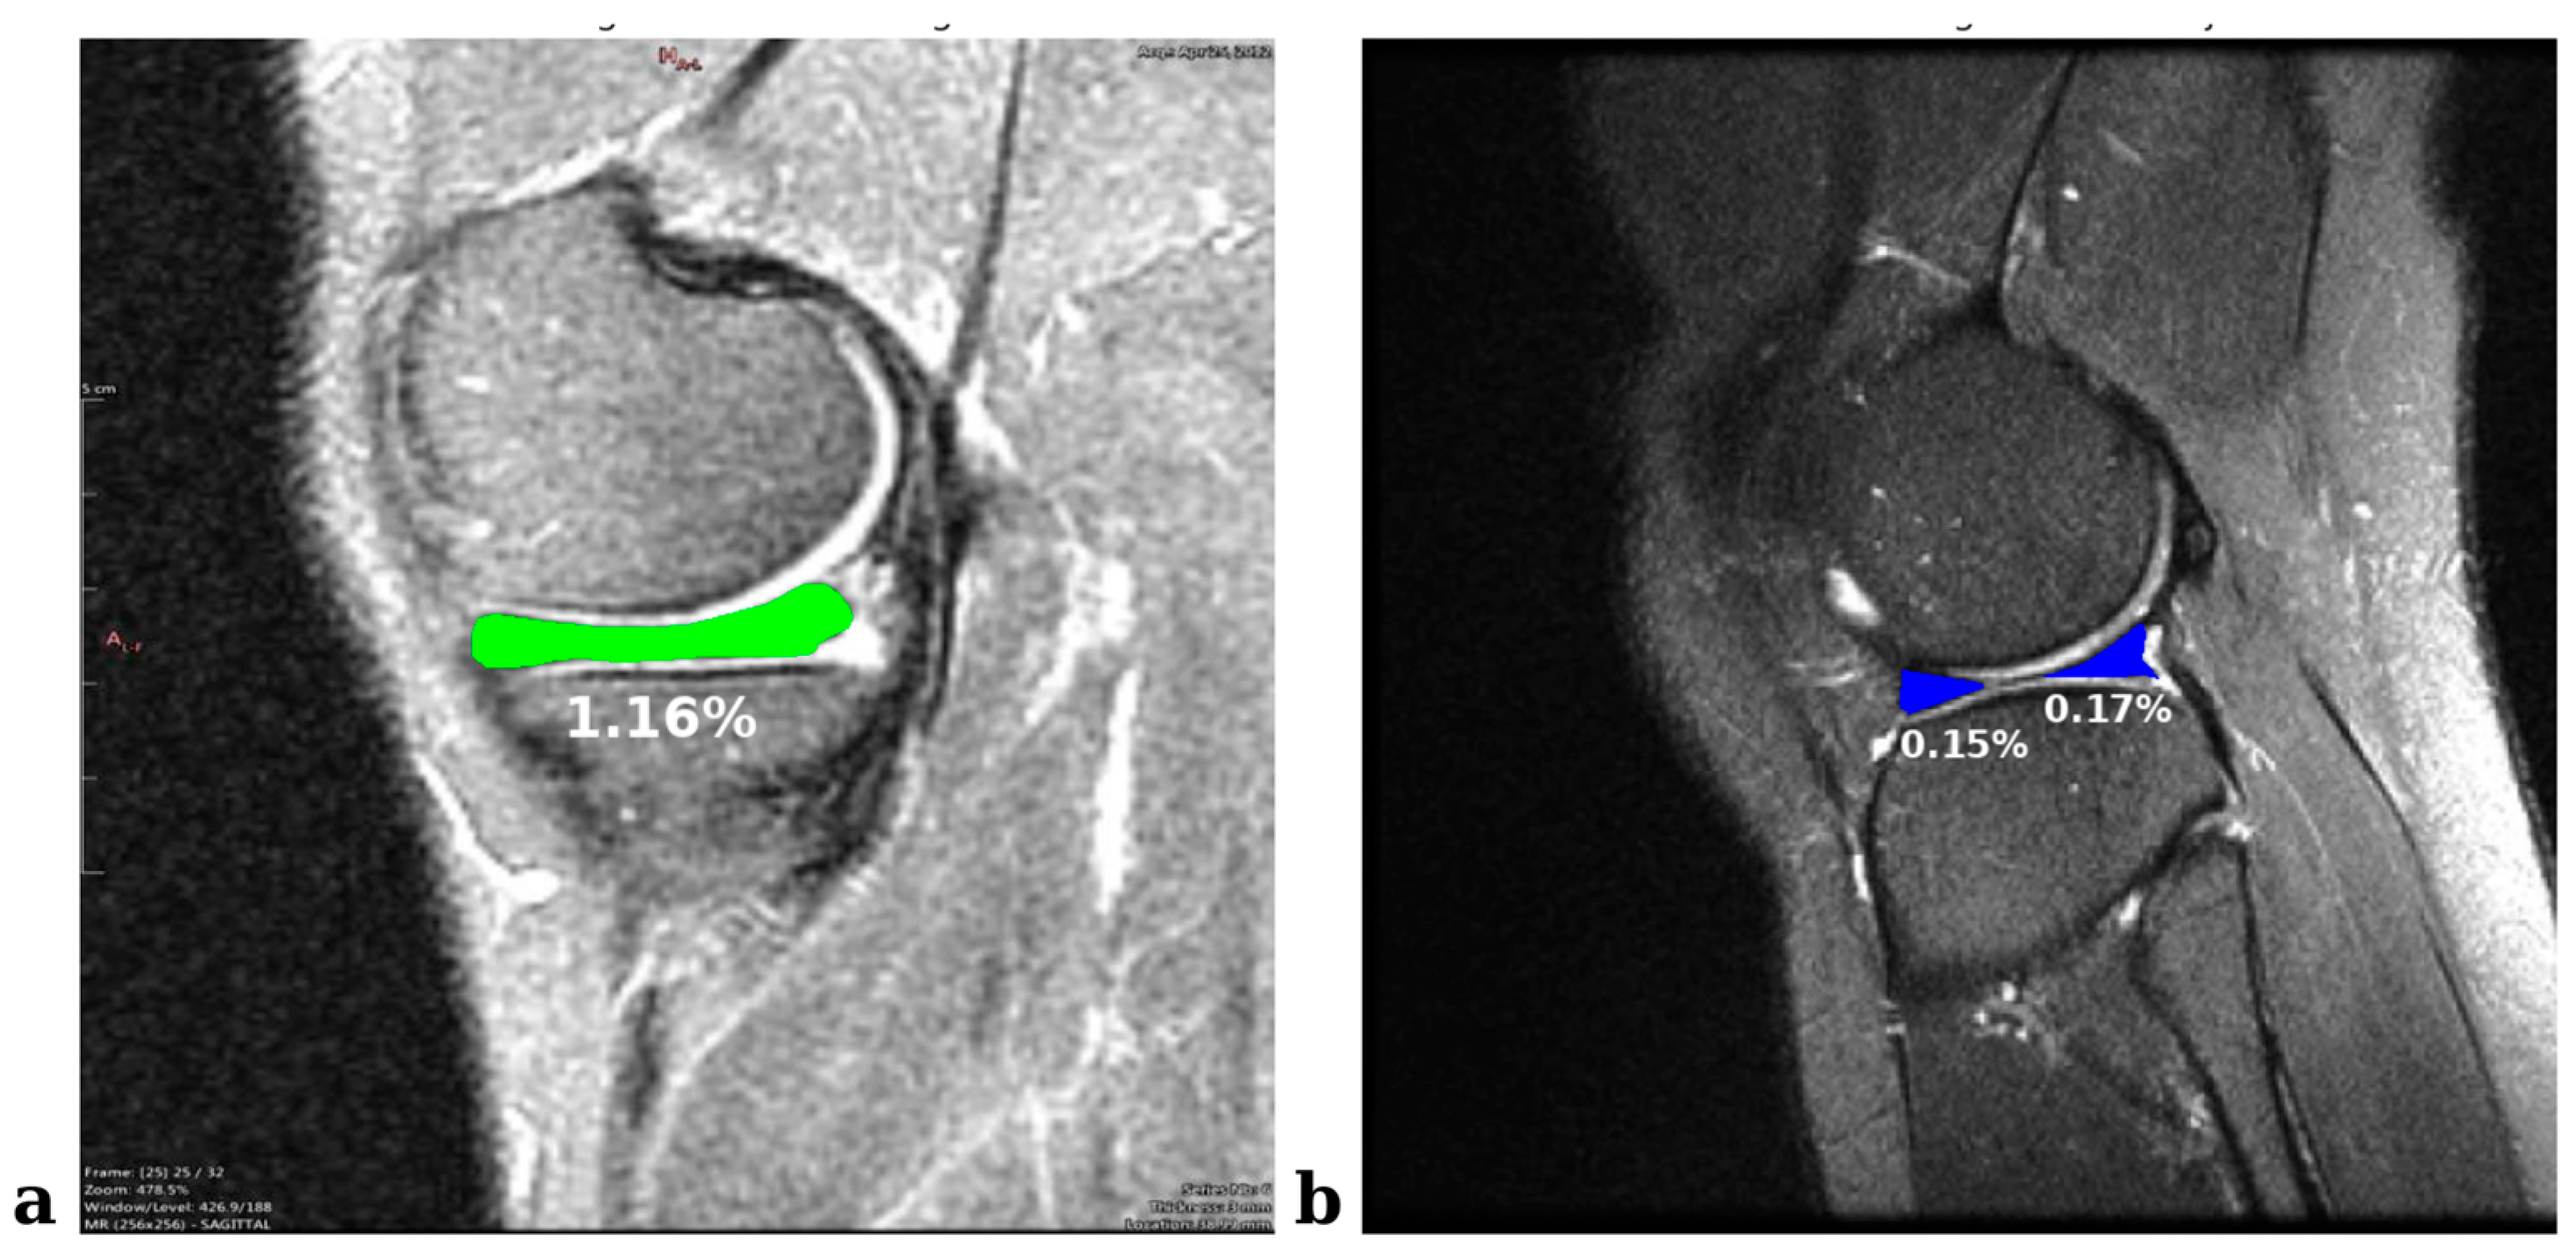

This study aims to extract meniscal ROIs from knee MRI images and improve segmentation results using ensemble-based approaches. We trained segmentation models based on state-of-the-art YOLO versions. We optimized the results using innovative ensemble methods such as pixel-based voting, weighted multiple voting, and dynamic weighted multiple voting with grid search. Meniscal volume is known to be less than 0.1% of the entire knee joint MRI scan [35] and, in the 2D images used in this study, meniscal ROI areas represent less than 1.5% (Figure 7). The manual segmentation of such small tissues has limited applicability due to its high risk of error and time-consuming nature. Therefore, deep learning-based approaches offer practical solutions to overcome these challenges. Furthermore, this is the first known study in which segmentation models based on the YOLO series are integrated with innovative ensemble methods (e.g., grid-search-based dynamic weighting) to improve performance.

Figure 7. An example of knee MRI images that represent the sizes of meniscal ROI areas. (a) Medial meniscus with meniscal tear in the internal set. (b) Healthy lateral meniscus in the external set.